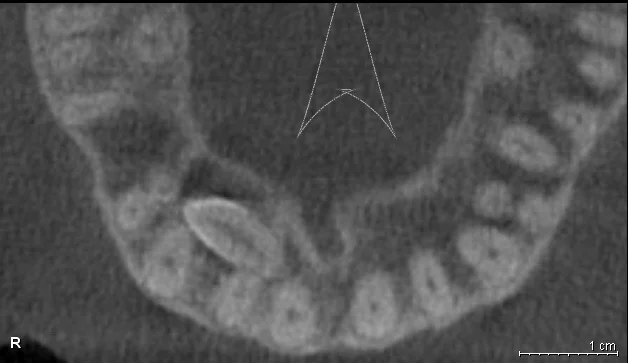

- Удобная программа обработки и просмотра изображения дает четкое понимание о состоянии проблемных зон, качестве и количестве кости, изогнутости корней зубов, анатомических особенностях расположения сосудов и нервов;

- Качественные трёхмерные снимки зубов дают возможность планировать весь процесс стоматологической реабилитации с высокой точностью и минимизировать процент возможных осложнений.

Воссоздавая орган (зуб) или даже совокупность органов, необходимо предельно точно знать исходную ситуацию. Корни зубов, каналы зубов, крупные сосудисто-нервные пучки, идущие внутри костной ткани, верхнечелюстная пазуха во всех подробностях и т.д. - в неискаженном виде все это можно увидеть только на компьютерной томограмме. Стоит ли говорить, что все эти структуры важны для имплантации, так как могут быть легко поврежденфы в ходе операции.